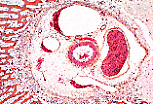

Au niveau du canal dentaire de cette dent incluse dans l'os maxillaire, s'observe une veine dite fibreuse, dénuée de paroi identifiable.

La paroi de cette veine, particulièrement bien protégée par l'environnement osseux, est pratiquement réduite à son endothélium.